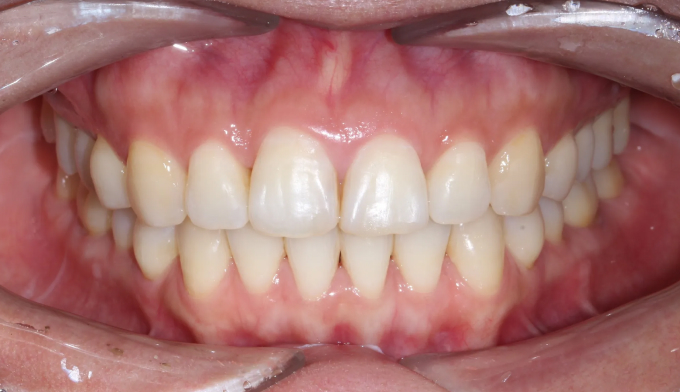

40대가 넘어가면서부터 앞니들이 점점 가운데로 몰리고 삐뚤빼뚤해지는 경우가 많습니다.

우리의 이들은 어릴적 맹출한 위치에 평생 있지 않고, 긴 시간에 걸쳐서 앞쪽으로 쏠리기 때문입니다.

삐뚤빼뚤한 정도가 심하지 않다면 간단한 앞니 부분교정만으로 충분히 배열이 가능하지만, 확보해야할 공간이 크다면 전체교정을 통해 어금니를 뒤로 보내야 앞니를 배열할 수 있는 공간을 만들 수 있습니다.

총 치료기간은 14개월 소요되었습니다.